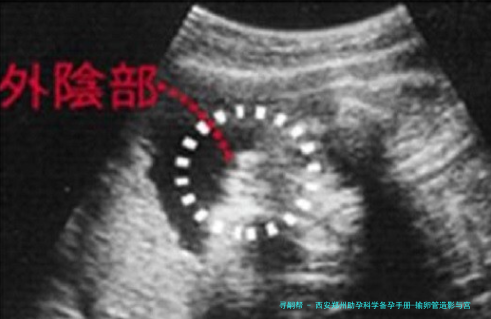

输卵管造影是一种评介输卵管通顺度的影像学检查。它并非将器械深入宫腔,而是通过宫颈向子宫腔体内注入造影剂,然后利用X光或超声技术,即时察看造影剂是否能够顺利通过输卵管并扩散至盆腔,进而评价输卵管是否通畅、阻塞的部位以及子宫腔的样子。